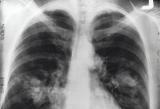

Исследование позволило установить 11 признаков и симптомов, наличие которых существенно увеличивает вероятность диагностики рака лёгких. Оно было основано на данных по нескольким десяткам тысяч человек...

В 2020 году рак легких стал главной причиной смерти от онкологических заболеваний. По данным Всемирной организации здравоохранения, болезнь унесла жизнь 1,8 млн человек. Неудивительно, что специалисты бьют...

Американские учёные выяснили что случаи рака лёгких у некурящих людей, вызываются опухолями, возникшими в результате генетических мутаций. Ранее выдвигалась точка зрения о том, что эти опухоли...

Исследователи мониторингового проекта Global Burden of Disease определили, что за прошедшие десять лет смертность в связи с раковыми и прочими видами опухолей, которые поражают органы дыхания, ориентировочно снизилась на...

Ученые корейского Университета Сонгюнгван, определили комбинацию препаратов, которая положительно сказывается на борьбе с раком легких., пишет РИА "Новости"...